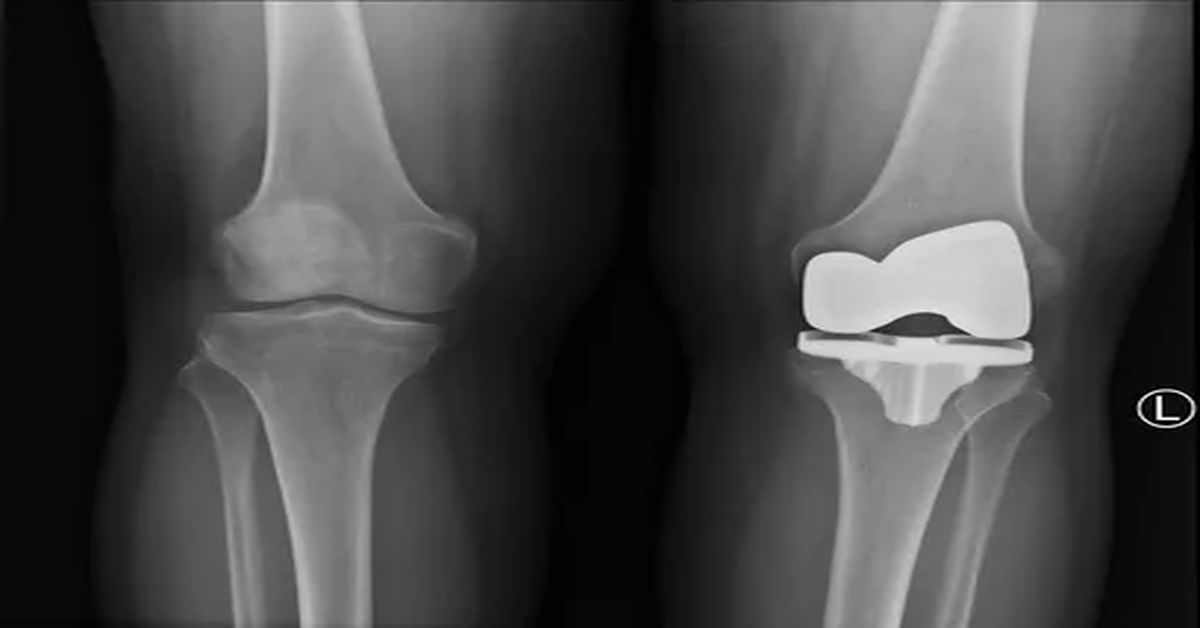

Eklem hastalıkları olan kişilerde uygulanan cerrahi yöntem, eklem yüzeylerini değiştirerek hareketi artırır ve ağrıyı azaltır. Total artroplasti, özellikle diz ve kalçada sık tercih edilir. Bu işlemde, hasarlı eklem parçaları özel protezlerle değiştirilir ve hastanın günlük yaşam kalitesi önemli ölçüde iyileşir.

Cerrahi sırasında eklem açılır ve hasarlı kıkırdak ile kemik dokusu dikkatlice çıkarılır. Gerekli ölçümler yapıldıktan sonra yapay eklem bileşenleri yerleştirilir. Bu bileşenler, genellikle metal karışımından üretilir. Uygulama sırasında kemik yüzeyine uygun bir şekilde yerleştirilir ve sabitlenir.